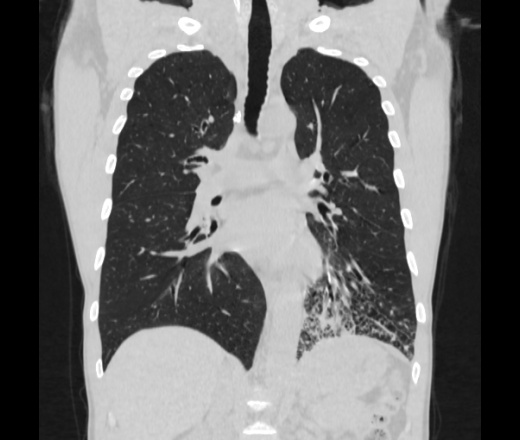

Мужчина пенсионного возраста. Цель назначения КТ ислючение зла в левом легком. Вижу тракционные бронхоэктазы с рубцовой эмфиземой по периферии, скорее всего БЭБ в стадии обострения. Дивертикулы трахеи. Выложил из за того что есть доля сомнения в отношении исключения зно3, немного смущают линии похожие на Керли.

Единственно, не сказал бы, что это тракционные бронхоэктазы, ну, и про линии Керли не вполне понял.

Ну да. Выразился не правильно. На фоне легочного рисунка усиленного линии похожие на септальные, не знаю как называются, при интерстиц.отеке похожие

На мой взгляд, это не главное, указал бы в описании - локально утолщен междольковый интерстиций, и всё